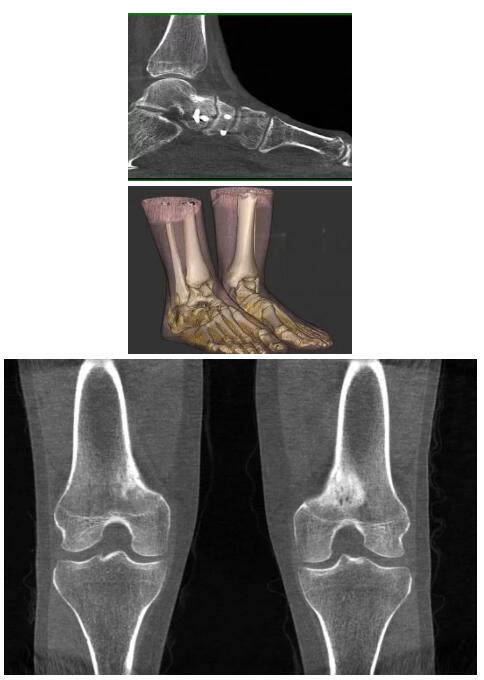

比如上面這款專用于足部和踝部掃查的CT成像系統(tǒng),患者在進(jìn)行CT掃查時(shí)只需要站在上面即可,雙腳站或者單腳站都可以,當(dāng)然,如果患者不是那么方便站著做完CT掃查,也可坐在上面。

這款CT掃查系統(tǒng)自帶屏蔽裝置,它的體積非常小,僅需要極小的空間即可,并不像常規(guī)CT那樣需要一間單獨(dú)的檢查室。此外,這種CT掃查的速度非???,僅需30秒左右可以完成檢查,輻射劑量相對常規(guī)的CT要少許多,尤其適合醫(yī)院的骨科使用。

而患者站著做足部或者踝部做CT檢查還有個(gè)好處是,可以檢查患者在負(fù)重的情況下,骨關(guān)節(jié)的真實(shí)情況,而躺著做CT掃查時(shí)未必能看出來。負(fù)重CT掃查特別是對于受傷的運(yùn)動員或者舞蹈員來說意義更大,能夠更準(zhǔn)確地評估傷情,幫助他們盡早復(fù)原。

以下是這些“特立獨(dú)行”的CT所拍出來的圖像: